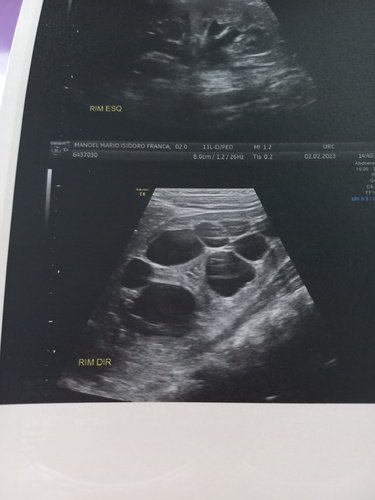

Eu sou Maria Luiza, sou de Balneário Rincão. Criei essa vakinha para meu filho MANOEL MÁRIO ISIDORO FRANÇA de 11 meses que desde a gravidez tem o rim direito dilatado e nesses últimos 2 meses esse rim dilatou o dobro. O doutor que acompanha ele desde o nascimento dele deu esses dois exames qua cada um sai em torno de 600 á 700 reais, e nesses dois exames ele vai ver se vai ser cirúrgico ou não mais ele tem pra ele que irá precisar de cirurgia. Então venho aqui pedir de coração que ajude a nós e principalmente a saúde do meu bebê.

Esse é a ecografia dos rins e das vias urinárias do Manoel: